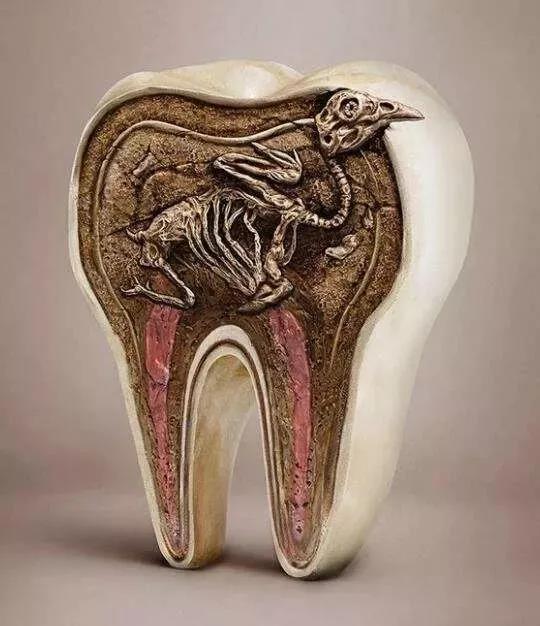

бРГнШБЪЇКѓЛсЖдКмЖрЙІФмВњЩњгАЯьЃЌБШШчОзНРЙІФмЪмЫ№ЃЌУЛгаНРЫщЕФЪГЮяжБНгНјШыЮИГІЕРЃЌЛсМгжиЮИГІЕРИКЕЃЃЛбРГнШБЪЇКѓгАЯьУРЙлКЭЗЂвєЙІФмЁЃМДЪЙЪЧЕЅИібРШБЪЇЃЌбРГнЯрЛЅжЎМфЕФСІСПДЋЕнвВЛсБЛДђЦЦЃЌдьГЩСкбРЕФЧуаБКЭЖдђЂбРЕФЙ§ГЄЃЌЧуаБвЦЮЛЕФбРГнЛсНјвЛВНИЩШХОзНРдЫЖЏбЛЗЃЌзюжеЕМжТвЇКЯИЩШХЛђДДЩЫЁЃМјгкбРГнАЮГ§ЛсДјРДвЛЯЕСаЕФЮЪЬтЃЌЫљвдФмЙЛБЃСєЕФЛМбРвЊОЁСПБЃСєЁЃ

авдЫЕФЪЧЫцзХПкЧЛБЃДцММЪѕЕФЗЂеЙЃЌКмЖрЙ§ШЅШЯЮЊВЛФмБЃСєЕФЛМбРЯждкЭЈЙ§жЮСЦФмЙЛЛжИДдгаЕФЙІФмЁЃБШШчЫЕвдЭљШЯЮЊБиаыАЮГ§ЕФВаИљЃЌФПЧАЭЈЙ§ИљЙмжЮСЦМгЩЯзЎКЫЙкаоИДОЭПЩвдЛжИДдгаЕФЙІФмаЮЬЌЃЛБШШчгабРжмбзЕФЛМепвВПЩвдЭЈЙ§бРжмЯЕЭГжЮСЦЃЌПижЦбРжмбзжЂЃЌзшЖЯбРжмбзНјеЙЃЌМѕЩйЛМбРЕФЫЩЖЏЃЌЛжИДЛМбРВПЗжЩѕжСШЋВПЙІФмЁЃ